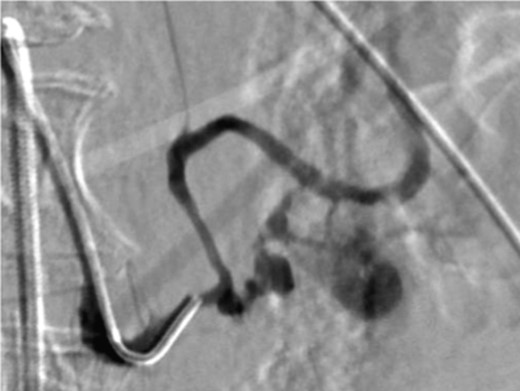

A frail 77-year-old multiparous Caucasian female with a history of aspirin and naproxen use, presented to an outside hospital with epigastric pain and an episode of hematemesis. She had no prior history of peptic ulcer disease, alcoholism or pancreatitis. The patient was hemodynamically stable with an acute anemia (hemoglobin of 7.7 g/dl), which prompted transfusion of 2 units of PRBC and transfer to a tertiary care facility. Upon transfer, she underwent an emergent upper endoscopy, which revealed a large amount of blood with clots in the lumen of the stomach. However, sufficient suctioning of the large intra-gastric clots was not possible; hence, an underlying etiology was not obtainable. The patient subsequently underwent a diagnostic angiography, which revealed a 4 cm mid-SA pseudoaneurysm with active contrast extravasation into the stomach which can be seen in Figs 1 and 2. The radiologist decided to perform a transcatheter arterial coil embolization of the artery to halt the active bleeding. A post procedure angiography revealed no further contrast extravasation. A planned upper endoscopy was repeated the following day that revealed some residual clotted blood in the stomach, no active bleeding and a deep 4 cm gastric ulcer. Due to the high risk of re-bleeding, the patient was optimized physiologically and consented and prepared for exploration. Intraoperatively we observed that the SA pseudoaneurysm was densely adherent to the posterior wall of the stomach, and coursing through an inflamed distal pancreas. We decided to proceed with an en bloc resection of SA pseudoaneurysm, distal pancreatectomy, partial gastrectomy and splenectomy. After the celiac axis was surgically defined, proximal and distal SA controls were obtained and a circumferential posterior gastrotomy was made. There was a visible posterior gastric mucosa to splenic arterial fistula, with the radiologically inserted embolic coils clearly visible. This can be seen in surgical specimen (Figs 3 and 4). Once the stomach was reflected, the splenic vessels and the pancreas were divided and the specimen removed. The pathology reports indicated active gastritis with transmural ulceration into the splenic artery (SA) and adjacent pancreatic tissue. No malignant cells were identified in the gastric or pancreatic tissue and the SA was not aneurysmal (Fig. 5). During the postoperative period, the patient had an uncomplicated recovery and was discharged on day 5.

Angiography image showing splenic artery pseudoaneurysm with contrast extravasation.